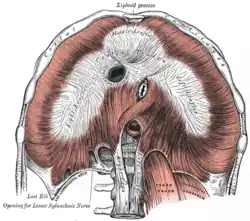

Superfície inferior do diafragma.

Superfície inferior do diafragma.